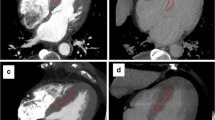

On first-pass CT images, the patients with CA exhibited a significantly lower SNRmyoc than the control subjects (Table 3). Myocardial attenuation was non-significantly lower in the patients with CA (p = 0.1). Blood pool attenuation, SNRblood and CNRblood-myoc were in the same range for both groups. On delayed CT images (Table 4), myocardial attenuation and SNRmyoc were significantly higher in the patients with CA than in the control patients. Blood pool attenuation and SNRblood were in the same range for both groups and consequently CNRblood-myoc was significantly lower in the patients with CA. The mean value of the RAI was 0.12 ± 0.25 in patients with CA. It was positive in all but two and reflected the increase in myocardial attenuation between first-pass and delayed images. In contrast, all the control patients exhibited a negative value of the RAI (mean value −0.56 ± 0.21) because their myocardial attenuation decreased between first-pass and delayed acquisitions. It was statistically (p < 0.05) lower than that of the patients with CA. Images of patients with CA and control patients are reported in Figs. 1, 2 and 3.

LGE MR images acquired in the four chamber (a) and in the short axis (b) planes showed heterogeneous myocardial enhancement of the left ventricle (arrowheads), right ventricle (arrows) and atria (double arrow) in one patient with CA. First-pass MDCT images (c) of the patient evidenced a global left ventricular thickening. On delayed MDCT images (d) a reduction of contrast between interventricular septum (arrowheads) and left ventricular blood (star) was detected. The myocardial SNRs were 3.3 and 11.5, respectively, for the first-pass and the delayed acquisition. The relative attenuation index was positive (0.28)

Another example of diffuse myocardial enhancement of the left ventricle (arrowheads), right ventricle (arrows) and atria (double arrow) associated with diffuse thickening of cardiac wall detected on four chamber (a) and short axis (b) LGE images in one patient with CA. A thickening of the left ventricular wall was detected on visual analysis of first-pass MDCT images (c). On delayed MDCT images a low contrast between interventricular septum (arrowheads) and blood pool (star) was observed. The myocardial SNRs were 2.7 and 11.4, respectively, for the first-pass and the delayed acquisition. The relative attenuation index was positive (0.30). Note that the patient with CA also exhibited a thickening of the right ventricular wall and the interatrial septum